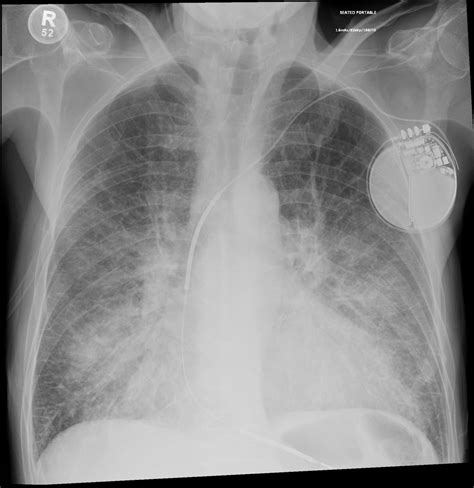

Chest X-rays are a cornerstone of medical diagnostics, acting as a quick and relatively inexpensive way to peek inside your chest. They use small doses of radiation to create images of your heart, lungs, blood vessels, and bones. These images can reveal a plethora of information, from detecting pneumonia and heart failure to spotting lung cancer and other abnormalities. In the context of pulmonary segments, chest X-rays help doctors identify which specific areas of the lung are affected by disease. For example, if a patient has a persistent cough and fever, a chest X-ray can show consolidation (a fancy word for lung tissue filled with fluid) in a particular segment, suggesting pneumonia in that area. This localization is incredibly valuable for diagnosis.

Start by identifying the major landmarks: the trachea, heart, diaphragm, and ribs. Then, focus on the lung fields themselves. Look for any areas of increased density (appearing whiter) or decreased density (appearing darker). These could indicate abnormalities within the segments. For example, a consolidation in the right upper lung field might suggest pneumonia in the apical or posterior segment of the right upper lobe. You’ll also need to mentally superimpose the anatomical map of the pulmonary segments onto the X-ray image. This takes practice, but there are plenty of resources available, including diagrams and online tutorials, that can help. Additionally, pay attention to the angles of the X-ray. A PA (posterior-anterior) view is standard, but sometimes a lateral view is also taken, which can provide a different perspective and help you better localize abnormalities. Remember, identifying pulmonary segments on a chest X-ray isn’t about memorizing exact locations; it’s about understanding the underlying anatomy and recognizing patterns of disease. With patience and persistence, you’ll become a pro at spotting those segments in no time.